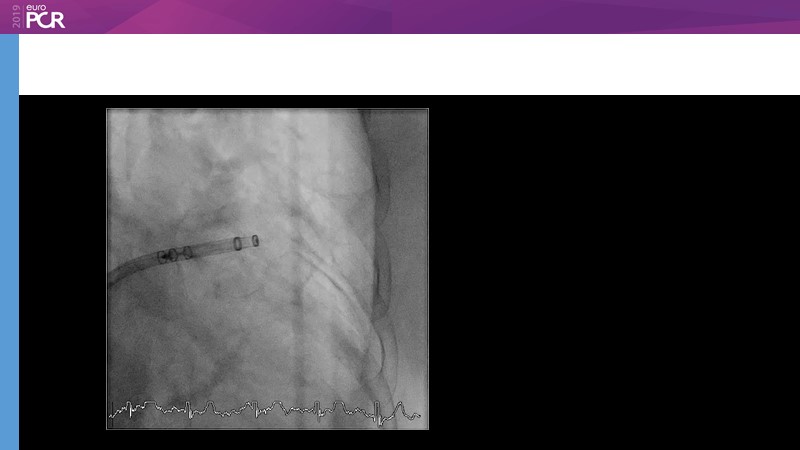

M. Sandri

Optimising procedural outcome and safety